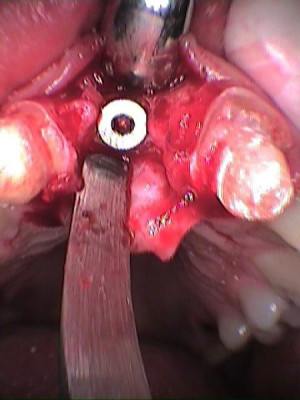

Implante colocado en incisivo central derecho

Secuencia de colocación de implante